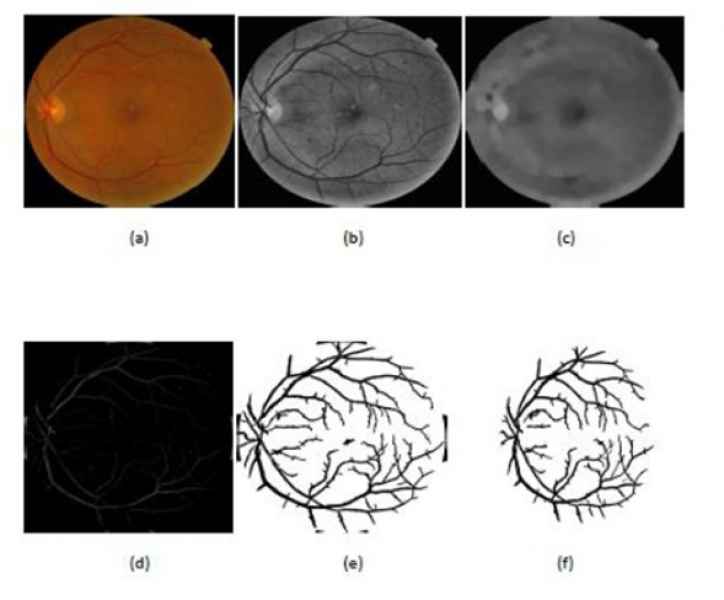

“Ahora lo que estoy trabajando es en el análisis de imágenes de fondo de ojo. Esas imágenes las clasifico en el grado de la enfermedad que tienen. La idea es hacer esto utilizando una tecnología llamada redes neuronales (subconjunto del machine learning) convolucionales, esto es para automatizar el proceso de detección”.

"Con este software que estoy haciendo, extraigo las venas, las aisló completamente del ojo y el médico puede hacer un análisis más detallado solo de las venas y también extraigo, exudados, micro aneurismas y las hemorragias en caso de existirlas". Dicho software aún se encuentra en proceso de pulimento.

Con un trabajo enfocado en la retinopatía diabética no proliferativa, y con el propósito de detectar la enfermedad preferentemente en una etapa moderada-leve, el estudiante de posgrado busca proponer un software en el que se pueda integrar toda la información en una aplicación de forma que sea amigable con el usuario final que sería el personal médico: